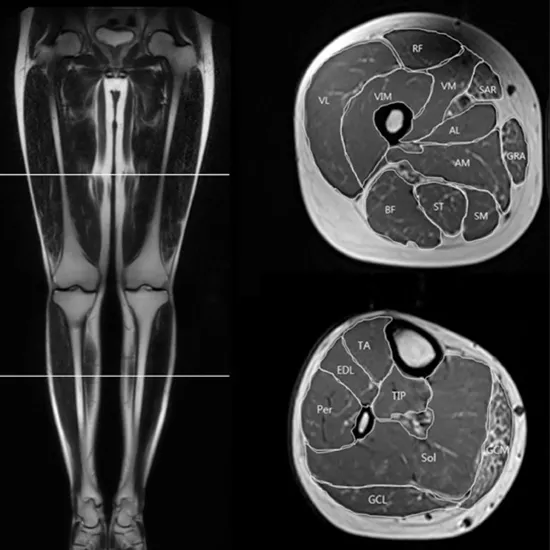

An extensive, detailed image of the bones, muscles, tendons, ligaments, cartilage, nerves, and lower limb blood flow is provided by lower leg MRI scans.

Lower leg MRI scan; non-invasive treatment to diagnose blood flow, tendons, muscles, cartilage, ligaments, and bone problems.